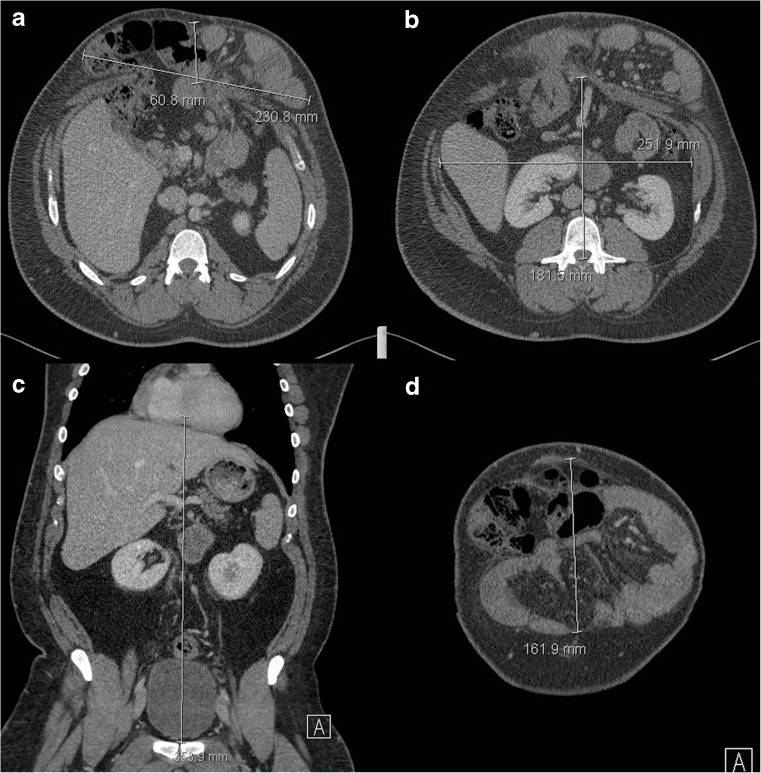

The CT dimension most used by surgeons is simply the maximum transverse diameter of the fascial defect, the “width”. In addition, we report the cranio-caudal dimension so that the surgeon has some advance information regarding the size of mesh that needs to be available (accounting for overlap if the mesh is not an inlay). Some workers report the cross-sectional area of the defect, but our surgeons do not find this adds anything substantial. CVH specialists will wish to know the relationship between hernia sac volume and the residual abdominopelvic cavity volume, a metric termed “loss of domain”. Loss of domain describes the extent to which the abdominal cavity has lost volume to the hernia and appears important when predicting the degree of systemic compromise that will arise when the hernia contents are returned to the abdominal cavity. Loss of domain was first calculated as the ratio arising when the hernia volume is divided by the residual abdominopelvic cavity volume, both calculated from CT scanning: 0.25 was used as the threshold to deploy preoperative abdominal tissue expanders in order to prepare for subsequent closure [12]. Subsequent workers have used a different metric, namely hernia volume divided by the total peritoneal volume (i.e. hernia volume and abdominopelvic volume), suggesting that >20% predicts difficulty with subsequent closure [22]. Calculating loss of domain by either method is achieved simply by measuring hernia dimensions, applying a factor to estimate ellipsoid volume (e.g. 0.52), and then doing the same for the abdominopelvic cavity (Fig. 7). Automatic segmentations to perform similar tasks have been described but are not available widely [23, 24]. Loss of domain has not been validated extensively nor are simple methods able to cope with unpredictable hernia shape. The effect of patient position on CVH morphology has not been studied, although our anecdotal experience would suggest many patients cannot lie prone.

Fig. 7.

Loss of domain calculation by CT. Figures a and b show measurement of hernia (231 x 61 mm) and abdominal cavity (252 x 182 mm) width and depth respectively. Figures c and d show measurement of abdominopelvic cavity (354 mm) and hernia (162 mm) cranio-caudal length respectively. Estimated hernia sac volume (HSV) = 231 × 61 × 162 × 0.52 = 1,187,026 mm3. Abdominal cavity volume (ACV) = 252 × 182 × 354 × 0.52 = 8,442,645 mm3. Total peritoneal volume (TPV) is 9,629,671 (i.e. HSV + ACV). Loss of domain by HSV / ACV ratio is therefore = 0.14 and 12% by HSV/TPV, suggesting that hernia repair will not result in serious cardiorespiratory compromise